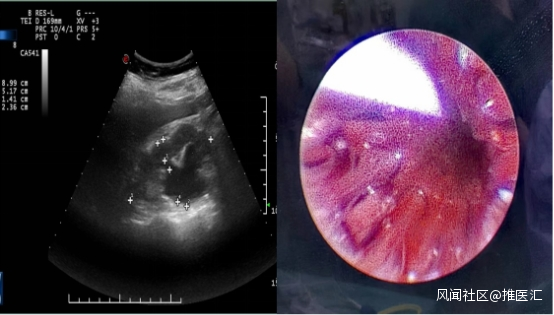

患者,女性, 3年前因宮頸癌在婦產科行宮頸癌根治性手術,術前檢查發現腹膜後淋巴結轉移遂術中留置輸尿管支架,後行放化療+免疫治療,術後患者出現腎積水(右側25mm),需定期更換雙J管支架。近1月出現腰痠腰痛、生活質量明顯下降,下肢水腫等症狀至六院泌尿外科就診。

經傅強主任診斷為宮頸癌晚期合併輸尿管狹窄,考慮到患者目前病情,傅強主任醫療團隊組織了針對該患者的病例討論,在與患者進行了充分溝通後,逐定於17日進行手術。術中醫生們無懼射線,反覆確認導管位置,進行了永久螺旋雙覆膜鎳鈦合金Allium支架置入。該病例是六院首例Allium支架輸尿管置入術,術後患者的輸尿管被擴張,順利排尿,快速為患者解除了燃眉之急。患者恢復良好,複查KUB片支架位置良好。輸尿管引流通暢,無明顯腰痛等不適症狀。